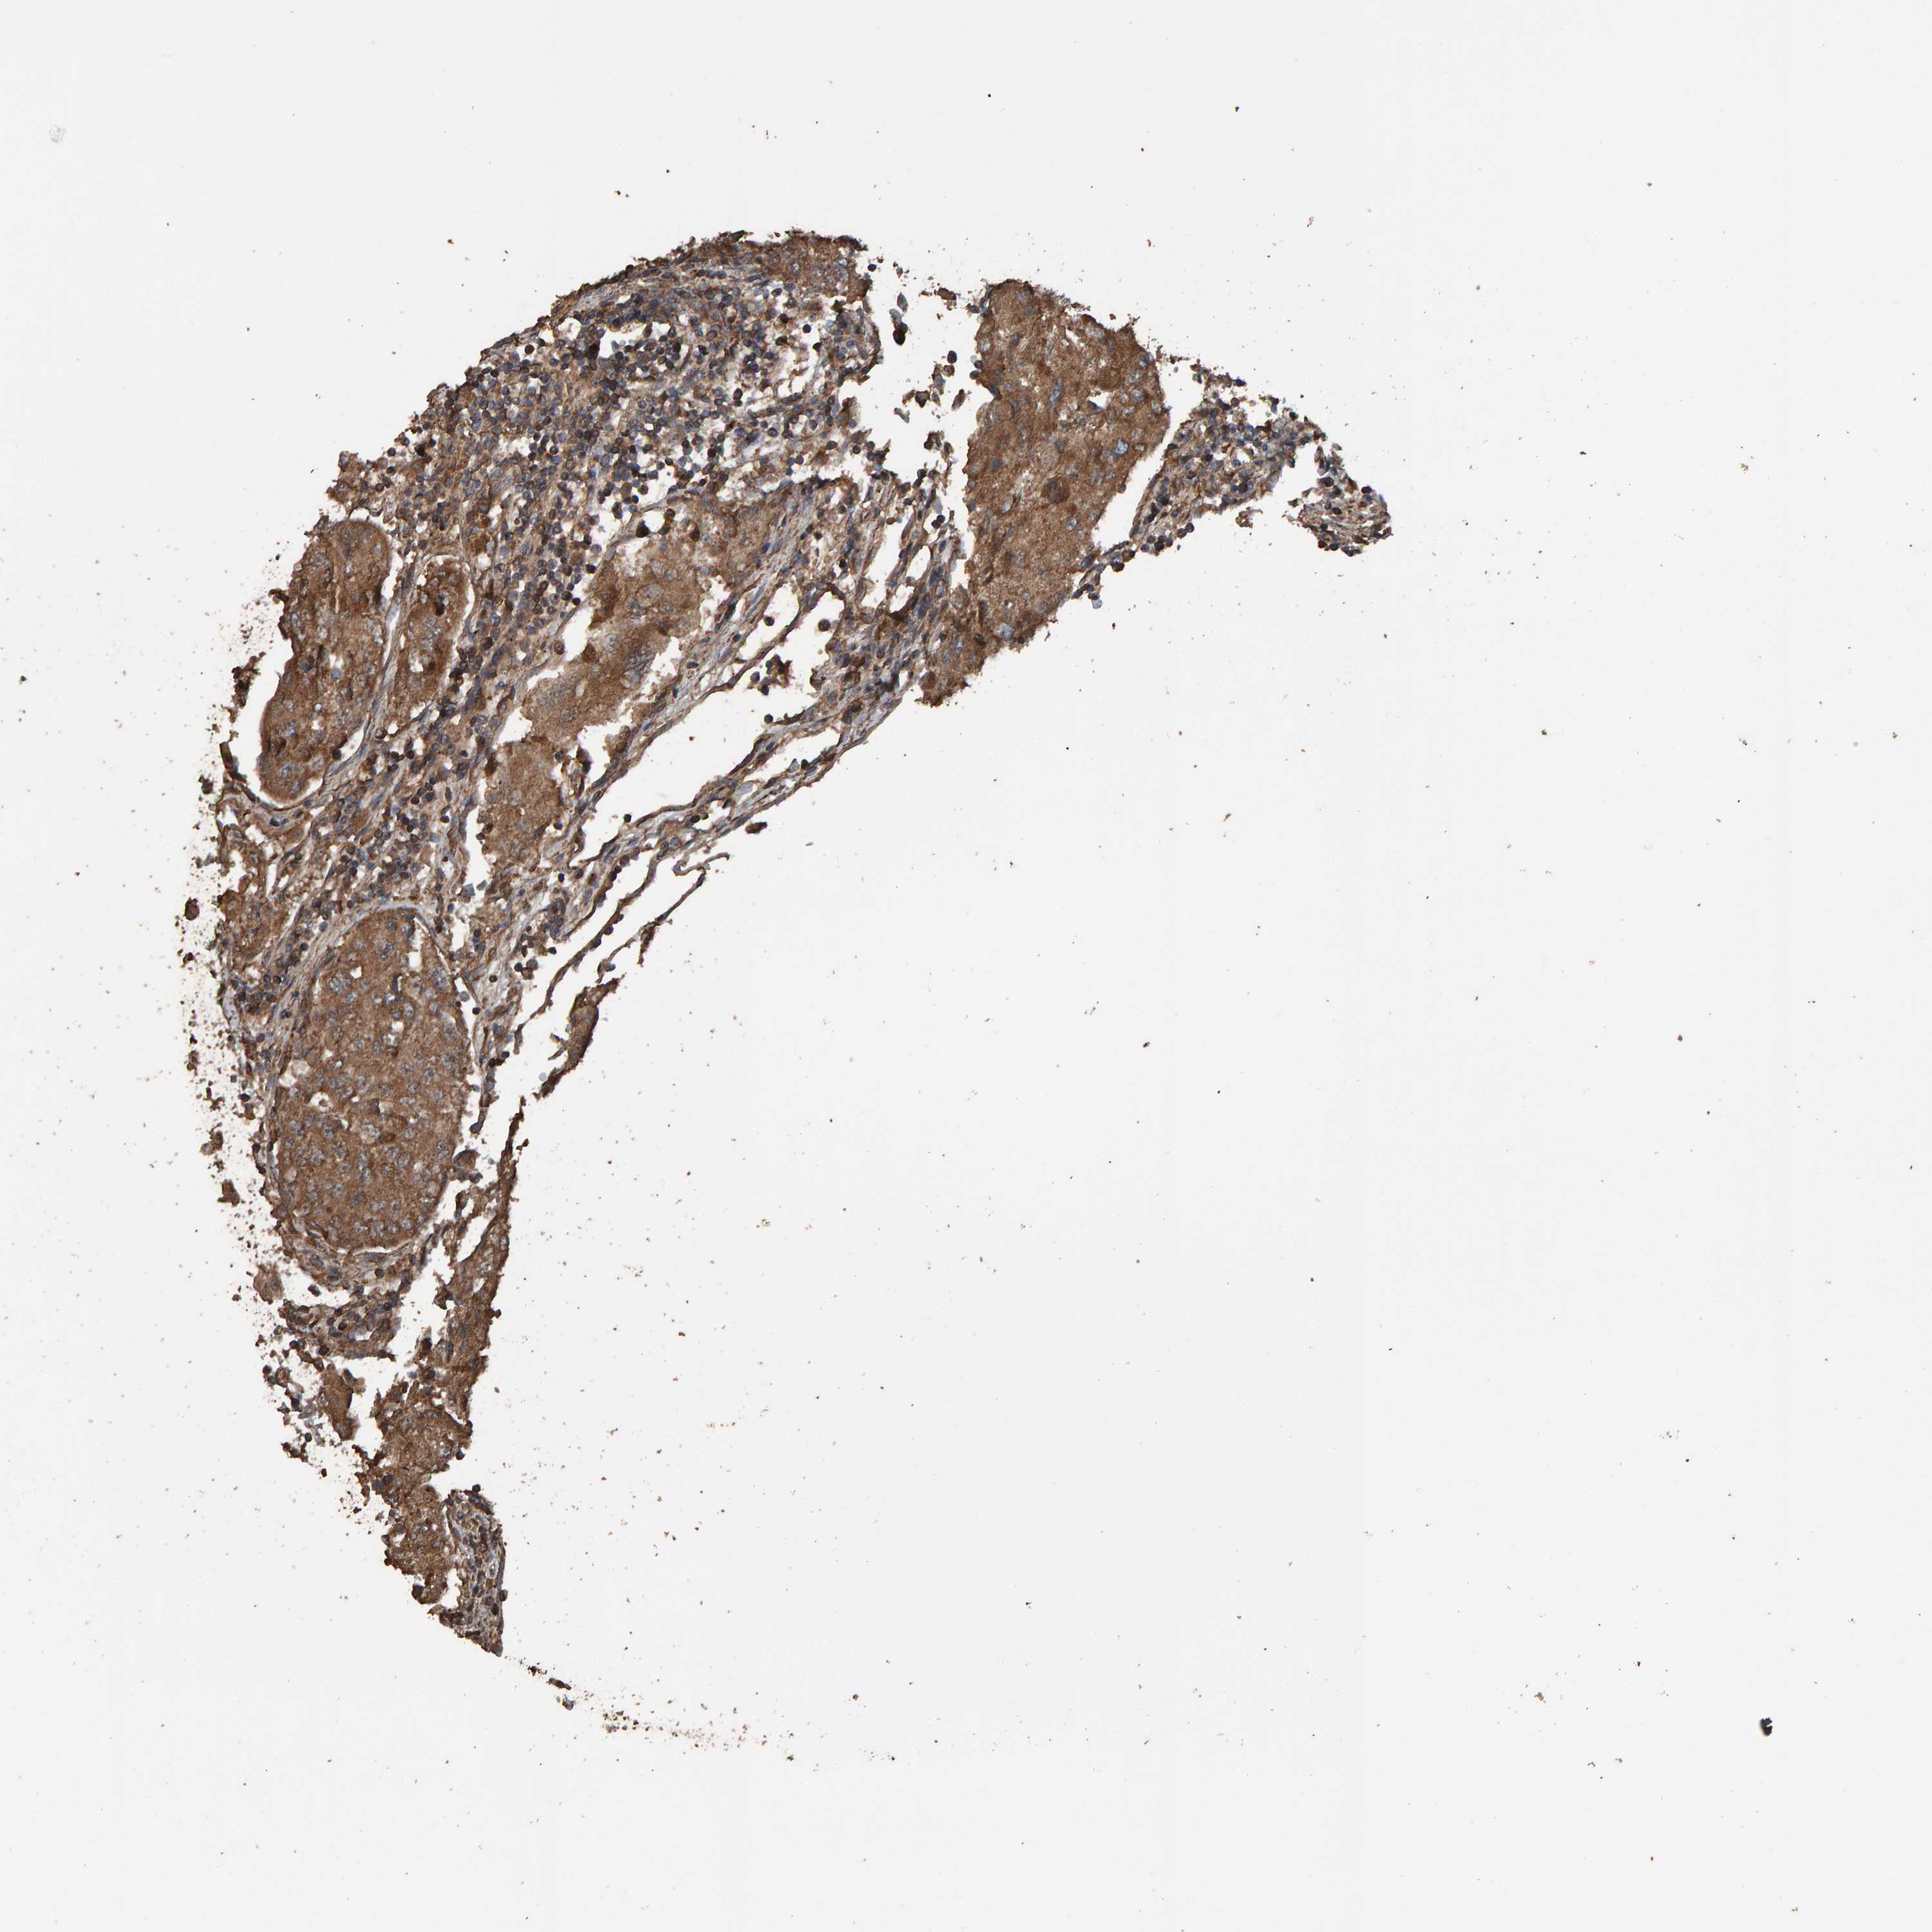

UROTHELIAL CANCER - Protein expressioni

A mouse-over function shows sample information and annotation data. Click on an image to view it in a full screen mode. Samples can be filtered based on level of antibody staining by selecting one or several of the following categories: high, medium, low and not detected. The assay and annotation is described here.

Antibody stainingi

Antibody staining in the annotated cell types in the current human tissue is reported as not detected, low, medium, or high, based on conventional immunohistochemistry profiling in selected tissues. This score is based on the combination of the staining intensity and fraction of stained cells.

Each image is clickable and will lead to virtual microscopy that enables deeper exploration of all samples and also displays staining intensity scores, fraction scores and subcellular localization as well as patient and tissue information for each sample.

Antibody HPA023384

Staining

High

Medium

Low

Not detected

Intensity

Strong

Moderate

Weak

Negative

Quantity

>75%

75%-25%

<25%

None

Location

Urothelial carcinoma, Low grade

Urothelial carcinoma, High grade